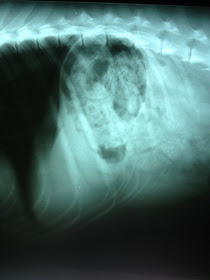

I rushed her to the vet and the x-ray showed a mass, which was thought to be food and/or shredded and chewed parts of the toy and the 2 squeakers. After 2 failed attempts to induce vomiting to bring up whatever was in her stomach, I was told she could be sedated and have a tube and camera inserted down her throat to try and locate/remove what was in it, but depending on what else was in the stomach there was no guarantee of success.

I rushed her to the vet and the x-ray showed a mass, which was thought to be food and/or shredded and chewed parts of the toy and the 2 squeakers. After 2 failed attempts to induce vomiting to bring up whatever was in her stomach, I was told she could be sedated and have a tube and camera inserted down her throat to try and locate/remove what was in it, but depending on what else was in the stomach there was no guarantee of success.

| My dogs stomach with mystery mass and 2 squeakers. |